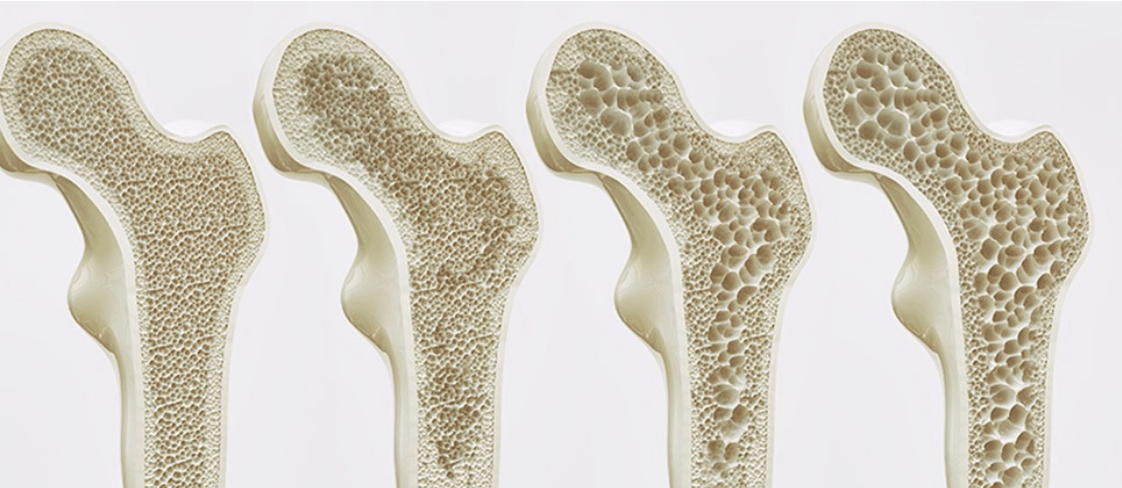

La osteoporosis es una enfermedad que cursa con pérdida de contenido mineral óseo y lleva a una debilidad en la microarquitectura del hueso, haciéndolo susceptible a fracturas. El hueso se vuelve más poroso (de ahí su nombre). Un hueso osteoporótico sería comparable a una tiza, fácil de romper.

Más allá de la simple pérdida de contenido mineral, la primera fase de esta patología es la osteopenia: pérdida de células óseas activas. Esta pérdida de células que producen hueso nuevo y reparan el dañado se correlaciona con una actividad sin carga (estilo de vida sedentario). La osteoporosis afecta al 25% de las mujeres y al 5% de los hombres mayores de 65 años. Pero no es un problema de la edad. Muchas personas de a partir de 40 años ya presentan una reducción de la densidad mineral en sus huesos.

Figura A: Hueso normal. Denso.

Figura B: Hueso osteoporótico y osteopénico. Poroso y frágil.